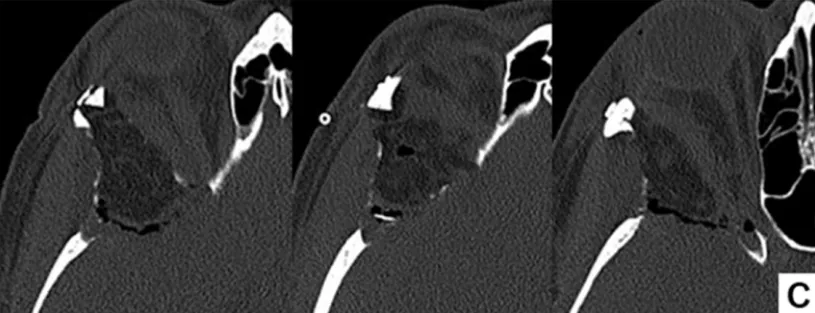

术后CT显示脑膜瘤和反应性增生的骨质均被完全切除。